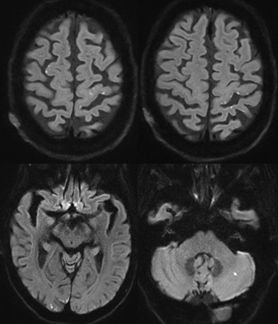

During her hospital stay, a brain magnetic resonance imaging (MRI) was obtained which revealed multiple punctate acute infarcts in bilateral frontal lobes, parieto-occipital lobes, and left cerebellar hemisphere (Figure 1). As the MRI findings were highly suggestive of cardioembolic stroke, a transthoracic echocardiogram was then performed which revealed a large, highly mobile mass attached to the interatrial septum that prolapsed into left ventricle during diastole. A transesophageal echocardiogram confirmed the left atrial mass (Figure 2). The patient underwent a successful surgical resection of the left atrial mass on hospital day 4, which was pathologically confirmed as a 4.0x2.5x1.9 cm cardiac myxoma. She was discharged on postoperative day 6 to home with asprin and atorvastatin for secondary stroke prevention. She has followed up in clinic for two years without recurrence of stroke.

Figure 1 MRI diffusion-weighted imaging revealing multiple punctate infarcts in bilateral frontal lobes, parieto-occipital lobes, and left cerebellar hemisphere.